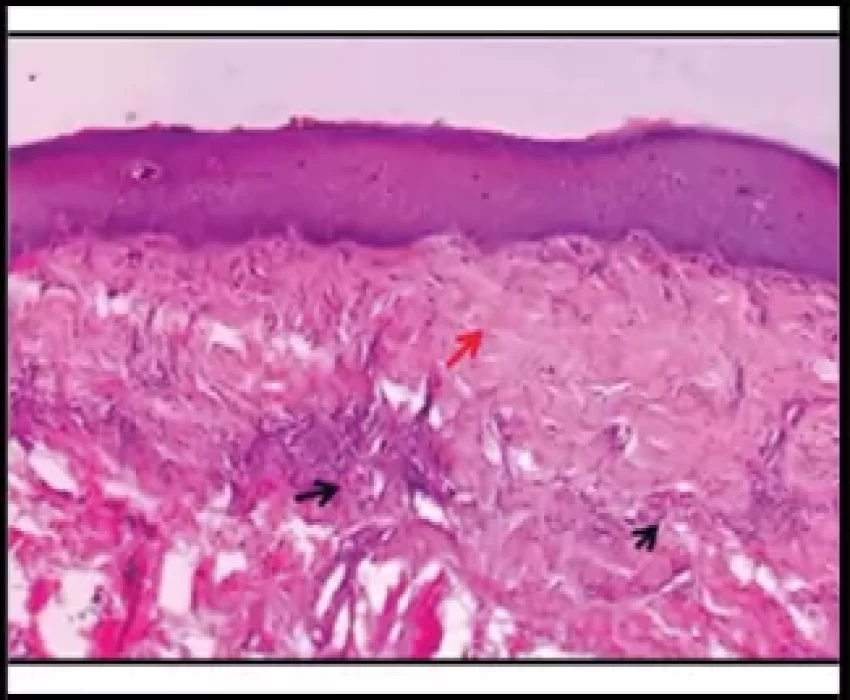

Oral Submucous Fibrosis (OSMF) is a precancerous condition and is mainly associated with the chewing of areca nut. This study was undertaken to correlate the etiological factors (duration, frequency, style and chewing habit) associated with OSMF with clinical grading and histological staging. The widespread habit of chewing gutkha plays a major role in the development of Oral Submucous Fibrosis than any other habit. The duration and frequency of its use and type of areca nut product has effect on the incidence and severity of OSMF.

The widespread habit of chewing gutkha has major role in the occurrence and severity of OSMF, especially in younger age group. The occurrence of OSMF in gutkha chewers is faster and more severe as compared to any other forms of areca nut products. The relative risk of disease increased with frequency and manner of chewing which conclude that the daily consumption rate appears to be relatively significant with respect to risk than the lifelong duration of habit. The histological grade should be considered as the gold standard in deciding the treatment plan and routine surveillance programme should be carried out in order to stop this perilous habit.